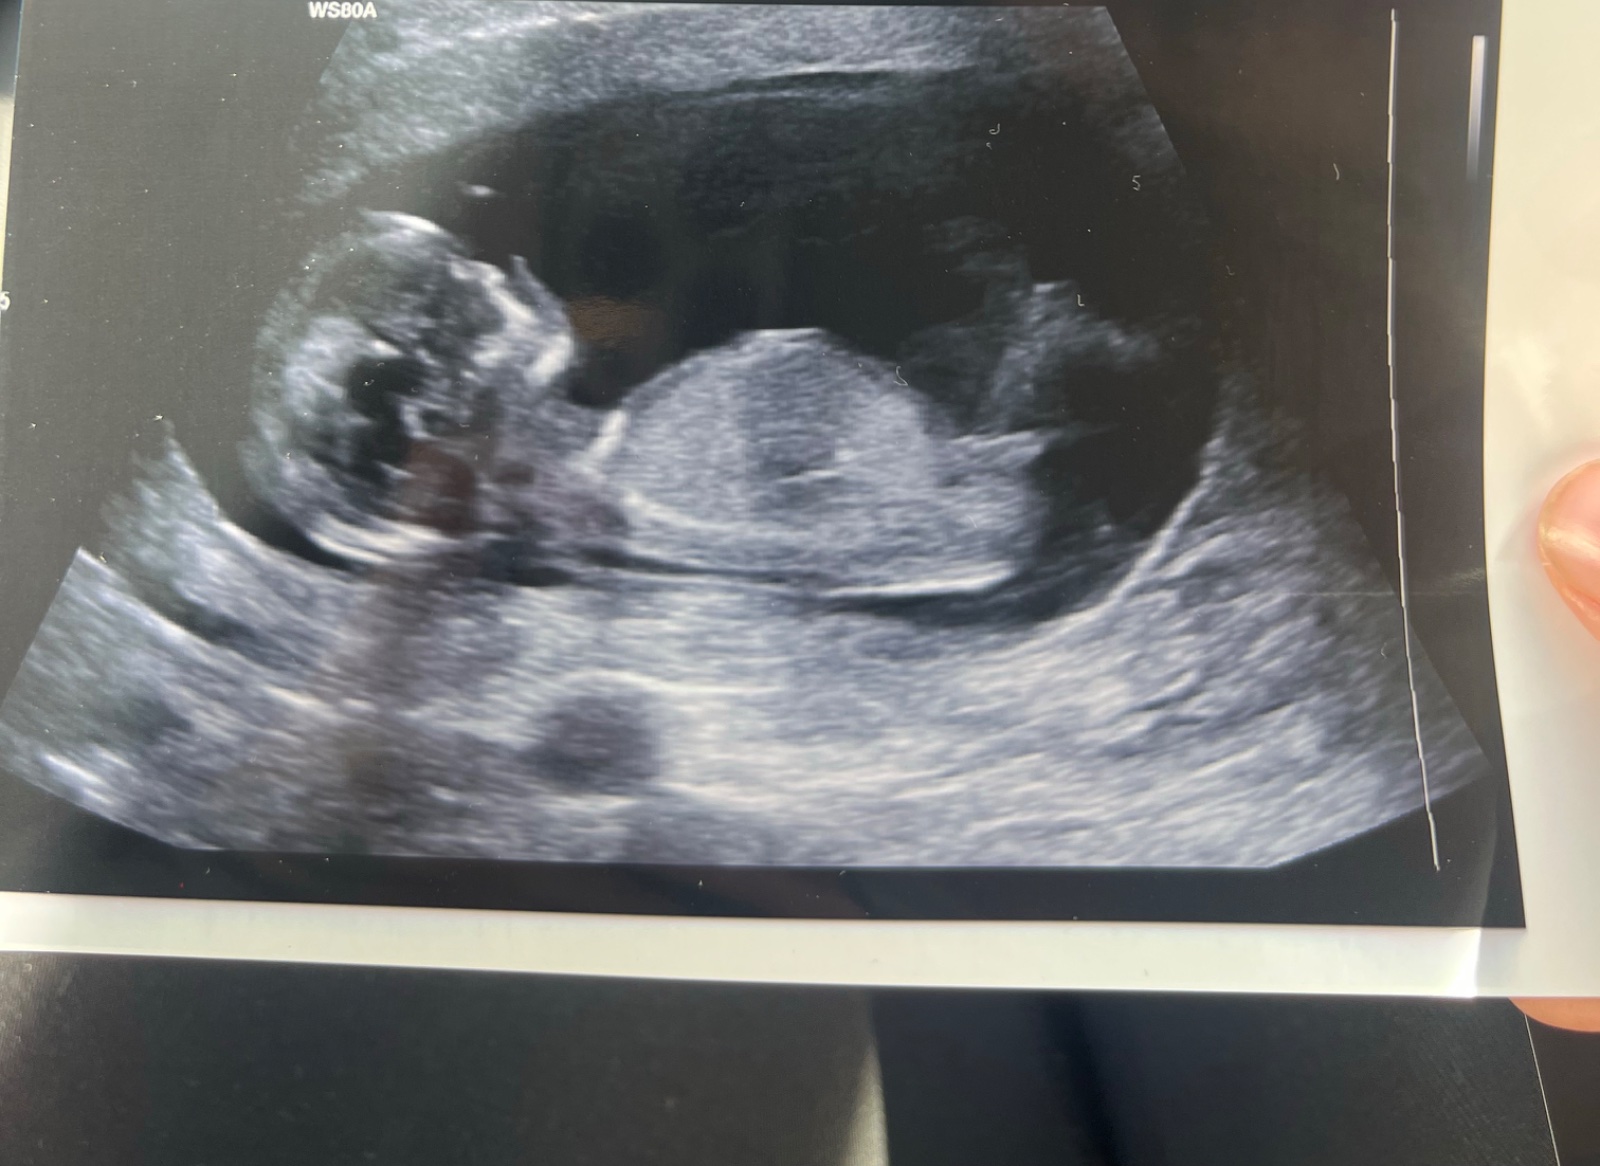

Může někdo určit pohlaví podle ultrazvuku ve 13+3 týdnu?

Prosím co by jste řekli u mě? 😁

Mě přijde, ze holka.

@ovesova taky bych řekla, ze holka... vypadá to stejně jako z naseho UZ ve 14tt 😃

@markeetaaa24 kluk. To pod pupečníkem trčí nahoru 😉

@hollynka myslim si, ze holka 🤗